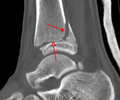

A triplane fracture of the ankle as seen on plain X-ray

A triplane fracture of the ankle as seen on CT